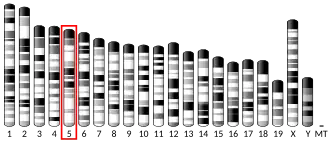

- Huppi K, Siwarski D, Pisegna JR, Wank S (Feb 1995). "Chromosomal localization of the gastric and brain receptors for cholecystokinin (CCKAR and CCKBR) in human and mouse". Genomics. 25 (3): 727–9. doi:10.1016/0888-7543(95)80018-H. PMC 6736545. PMID 7759110.

- de Weerth A, Pisegna JR, Huppi K, Wank SA (Jul 1993). "Molecular cloning, functional expression and chromosomal localization of the human cholecystokinin type A receptor". Biochemical and Biophysical Research Communications. 194 (2): 811–8. doi:10.1006/bbrc.1993.1894. PMID 8343165.

- Inoue H, Iannotti CA, Welling CM, Veile R, Donis-Keller H, Permutt MA (Jun 1997). "Human cholecystokinin type A receptor gene: cytogenetic localization, physical mapping, and identification of two missense variants in patients with obesity and non-insulin-dependent diabetes mellitus (NIDDM)". Genomics. 42 (2): 331–5. doi:10.1006/geno.1997.4749. PMID 9192855.